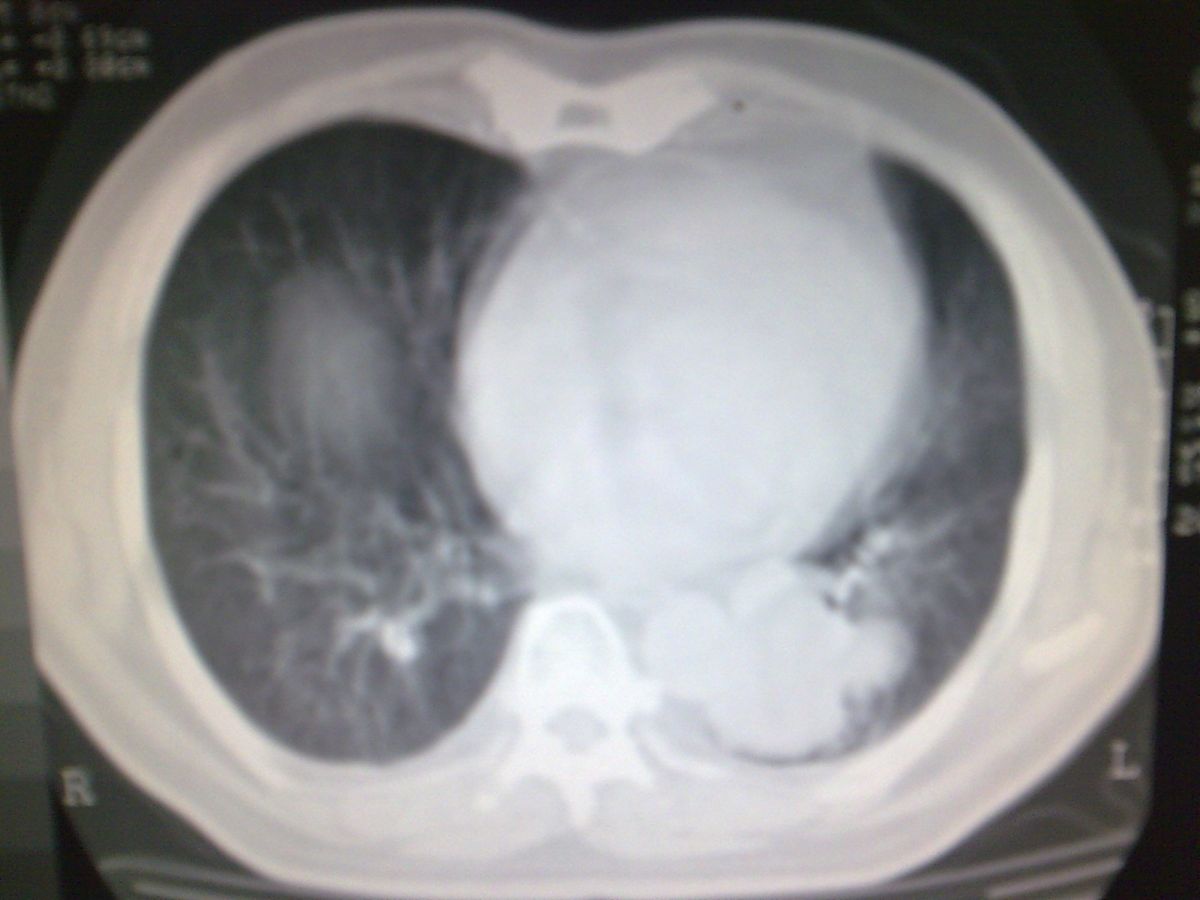

标题: CT19282:男性,70岁,咳血, [打印本页]

标题: CT19282:男性,70岁,咳血,

图片少了些,考虑周围性肺癌

考虑周围性肺癌

周围型肺癌。

考虑周围型肺癌,还是做增强扫描吧。

考虑左下肺周围性肺癌。

隔离症不像吗.周围型肺癌?还是做增强扫描吧。

肺隔离症不除外建议增强扫描

考虑左肺下叶周围型肺癌可能。